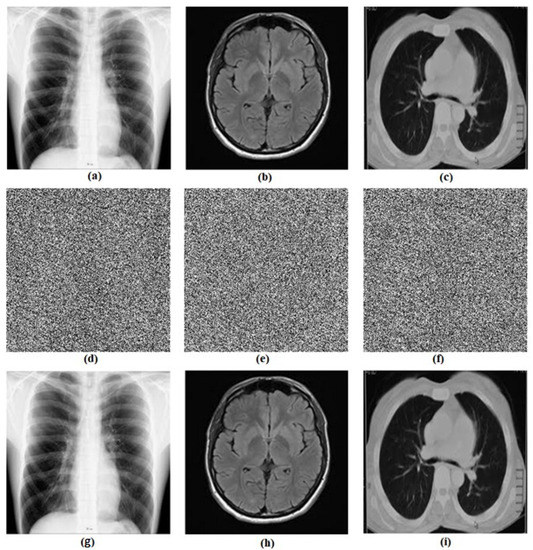

5. Biomedical Images Encryption Based on RNG Obtained from the Oscillator

5.1. Proposed Biomedical Images Encryption Algorithm

5.2. Computational Results

5.3. Security and Performance Analysis

5.3.3. Information Entropy